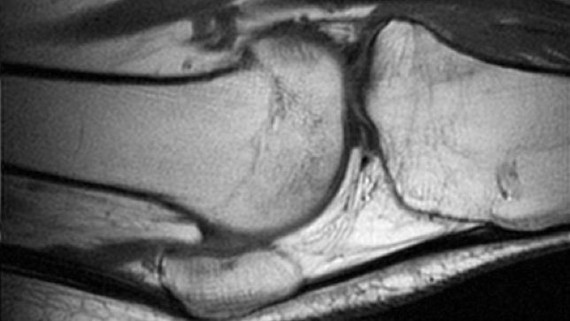

A su vez, se demostró también una mejora de la calidad del cartílago articular (de un 27 % de media) por técnicas de resonancia magnética cuantitativa en 11 de los 12 pacientes del ensayo clínico. Esta modalidad de terapia celular utiliza el mismo tipo de células que se utilizaron con éxito para el tratamiento del dolor lumbar causado por degeneración discal en un ensayo clínico publicado por los mismos autores en el año 2011.